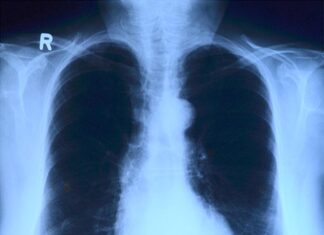

Что надо знать о туберкулезе

24 марта мир отмечает День борьбы с туберкулезом. Всемирная организация здравоохранения разработала стратегию, которая направлена на снижение смертности от туберкулеза и сокращение новых случаев заболевания, а также на максимальное обеспечение граждан дорогостоящими лекарствами, чтобы...